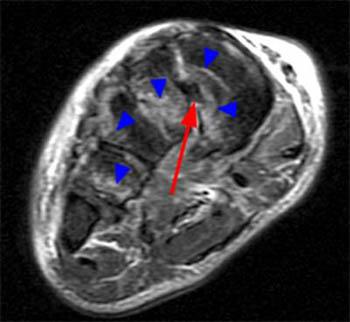

Attachments edit  extends from the external occipital protuberance on the skull and median nuchal line, to the spinous process of c7. Lisfranc Ligament Tear - Radsource

Lisfranc Ligament Tear - Radsource from radsource.us